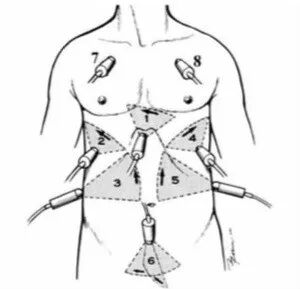

RUSH方案是从泵、容量和血管三方面进行休克的超声鉴别(详见下图)。对于低血容量性休克,心脏收缩功能较强,心腔变小;容量上表现为下腔静脉或颈内静脉扁平。心源休克是心脏收缩功很差,心腔扩大,容量上可以看到下腔静脉或颈内静脉明显扩张,肺部超声可见弥漫的B线。导致梗阻性休克的原因可能有的征象:心包积液、右室压力负荷增加,肺超声可能会看到气胸表现,肺滑动征消失,出现肺点;如果有肺栓塞,下肢血管彩超可能会看到血栓。分布性休克的特点并不是很突出,所以在诊断流程中,首先要进行简单的心脏超声和BLUE方案以除外梗阻性休克,如果正常,通过BLUE方案排除心源性休克(有无心脏超声异常以及肺水肿B线),如果正常,且主要为A线,此时可以进行液体复苏,如果纠正,则支持低血容量性休克;如果没有纠正,而且补液已经出现肺水肿,循环仍未得到改善,则需要考虑分布性休克(如脓毒症休克)的可能,此时超声也可能会检测到一些化脓感染的表现。

图片